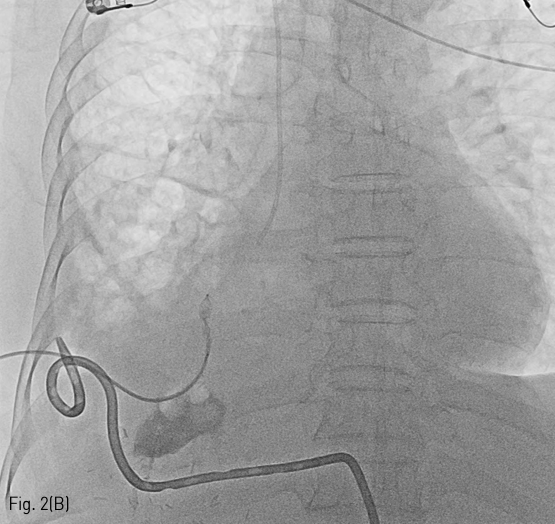

Fig 2B

A radiographic image of embolization of communicated bronchus using vascular plug (B).